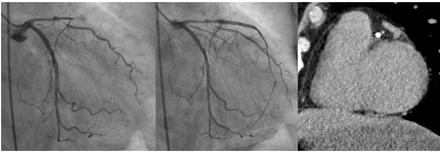

Reperfusion therapy such as percutaneous coronary intervention (PCI) is widely used in patients with acute myocardial infarction (AMI). While hemorrhagic transformation is frequently discussed in cerebral infarction following reperfusion, little attention has been given to hemorrhagic infarction in the setting of AMI. Clinically, we noticed that some patients exhibited transient ST re-elevation immediately after reperfusion, whereas others did not. This observation prompted us to investigate the potential relationship between transient ST re-elevation and the presence of myocardial hemorrhage. To this end, we performed contrast-enhanced CT scanning shortly after reperfusion therapy to evaluate myocardial bleeding.

We enrolled patients diagnosed with AMI with proximal lesions in the left anterior descending artery. A CT scan was conducted within 10 minutes of the final coronary angiography to visualize dye accumulation from the base to the apex of the left ventricle. Myocardial hemorrhage was defined based on CT density: an area more than 20 Hounsfield Units (HU) above the density of the non-infarcted myocardium and less than 400 HU, to avoid interference from stents or calcifications.

A total of 39 patients were studied. Among them, 11 exhibited transient ST re-elevation following reperfusion (re-elevation group), while the remaining 28 did not (no re-elevation group). In the re-elevation group, the dye volume index ranged from 9.38 to 25.46 ml/m2, whereas in the no re-elevation group, it ranged from 0 to 10 ml/m2. The difference was statistically significant, suggesting that re-elevation was associated with greater myocardial dye accumulation. Moreover, penetrating myocardial pigment elevation was frequently seen in the re-elevation group but was absent in the no re-elevation group.

CT imaging performed shortly after reperfusion therapy in AMI patients can help detect myocardial hemorrhage. The presence of transient ST re-elevation immediately after reperfusion may serve as a clinical indicator of myocardial hemorrhage, which tends to be transmural in such cases.